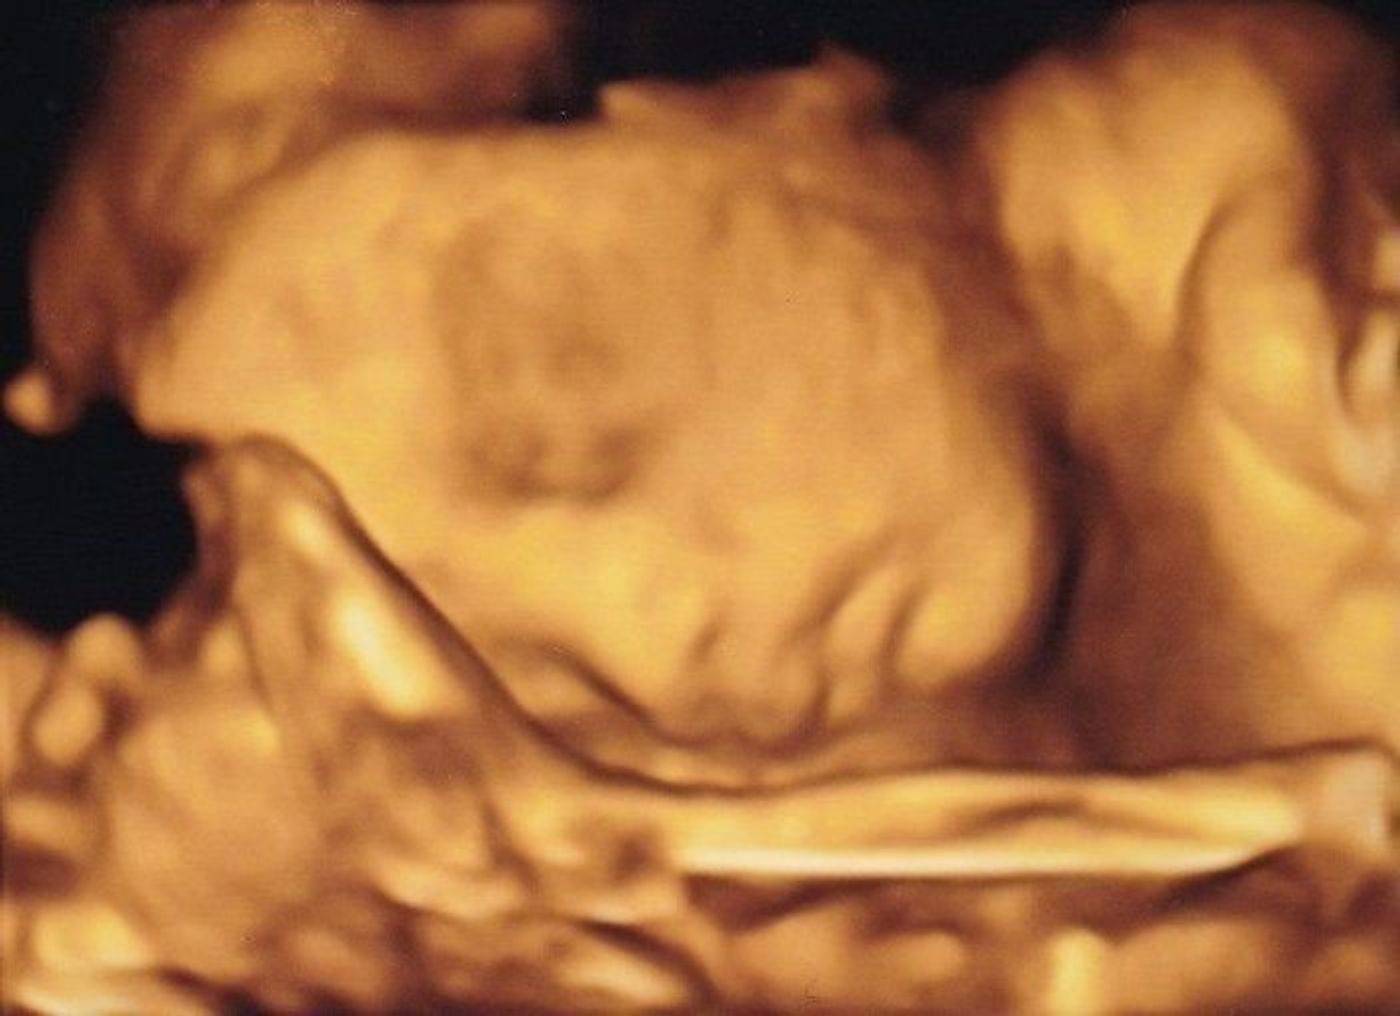

ママと赤ちゃんを結ぶ最初の体験として、胎動カウントを始めてみましょう! 妊娠28週目の赤ちゃんの大きさは? 妊娠28週目の赤ちゃんの大きさは レタスぐらいの大きさになっています。妊娠28 妊娠28週の赤ちゃんの様子 からだだけでなく脳も育つ時期。 聴覚に続いて視覚や嗅覚の発達も 28週のエコー写真。 手と足が顔の前にあって、まるで柔軟体操をしているようです 画6/3/19 出産まで3カ月は胎児の体重がまだ半分 注意点は 年齢別特集 妊娠・育休中のママ・パパ向け(1)34~36週で生まれたら「後期早産児」としてケアが必要。 ワクチン接種も 妊娠後

ねんれい 28 妊娠週 28w4d 上が4Dで下が2Dエコーです。 4Dエコーでは顔をママのお腹にくっつけてたのであんまり映らず、、、 (/_;) でもお口をモグモグしたりあくびしている姿を見れました♡ねんれい 27 妊娠週 28w3d 2週間ぶりの健診でした♪健診に行く期間が近くなって楽しみです (*^ ^*)頭のエコー写真です! 体重は1,230gで順調とのことです (*^^*)ちょっと胎動がまだか弱くて心12/7/ 3Dエコー写真のおすすめ時期は 早くても妊娠14週から、遅くても32週ごろ と言われています。 赤ちゃんの成長によって見え方が変わってきます。 全身を見たいか、顔の表情だけで十